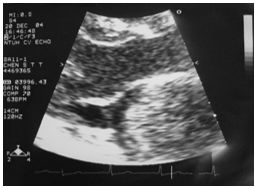

3. 病人18歲女計程車無線呼叫員, 到院主訴有五天的間 歇性燒熱及寒顫(chillness), 並合併頭痛、雙眼後疼痛及全身肌疼, 經初步診斷腦膜炎, 病人拒絕腰椎穿刺檢查, 乃試用抗生素後回家療養。 唯症狀仍舊, 尚有噁心、嘔吐, 並先後在左大拇指及右小趾出現疼痛紅斑(如圖A及B所示)。既往病史有二尖瓣膜脫垂及閉鎖不全。理學所見身高:162cm;體重:45Kg;BP:105/67mmgHg;T/P/R: 39.8C/155/18。未見Meningeal signs. 頸部末見異常, 心尖在left 5th ICS, mid-clavicular line, 有Grade III/VI Pansystolic murmur. S1及S2正常。胸、腹都無不正常。實驗室檢查: WBC:4.39x k/uL,有left shifting;RBC:5.12 x M/uL;Hb:11.0 g/dL;Platelets:130 x K/uL;其血液細菌培養結果如與胸部X光詳見附圖C、D。心電圖如附。本病人經過下列臨床處置